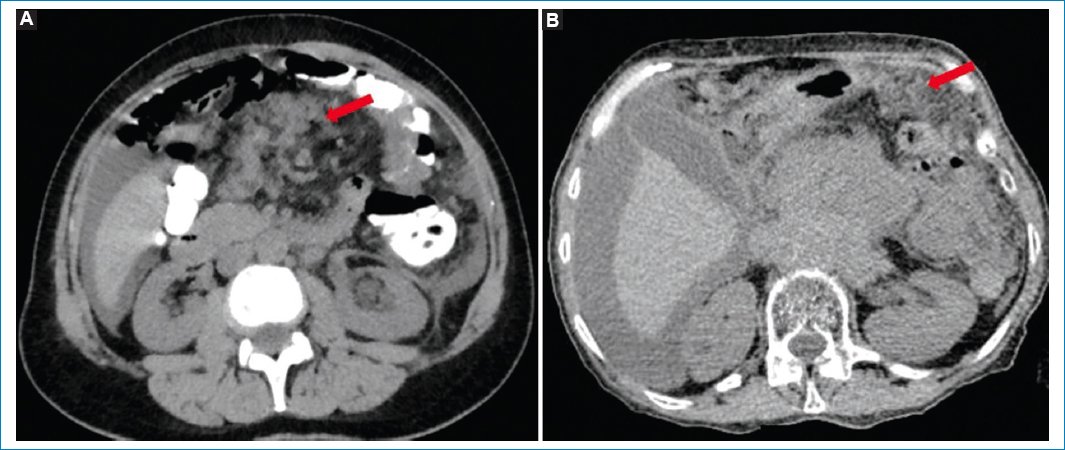

Figura 6. Varón de 74 años con diagnóstico de linfoma no Hodgkin difuso de células B en recaída, con LP. Imágenes axiales de TC (A) y fusión PET-TC (B) que evidencian engrosamiento nodular del peritoneo y de la fascia pararrenal anterior, con aumento de consumo de 18F-FDG (flecha).

Figura 7. Varón de 65 años con diagnóstico de linfoma difuso de células B grandes y LP. Imágenes de TC (A), fusión PET-TC (B) y MIP (C y D) en las que se puede observar el patrón nodular hipermetabólico del peritoneo (flecha azul) y las adenomegalias en múltiples lugares (flecha roja).